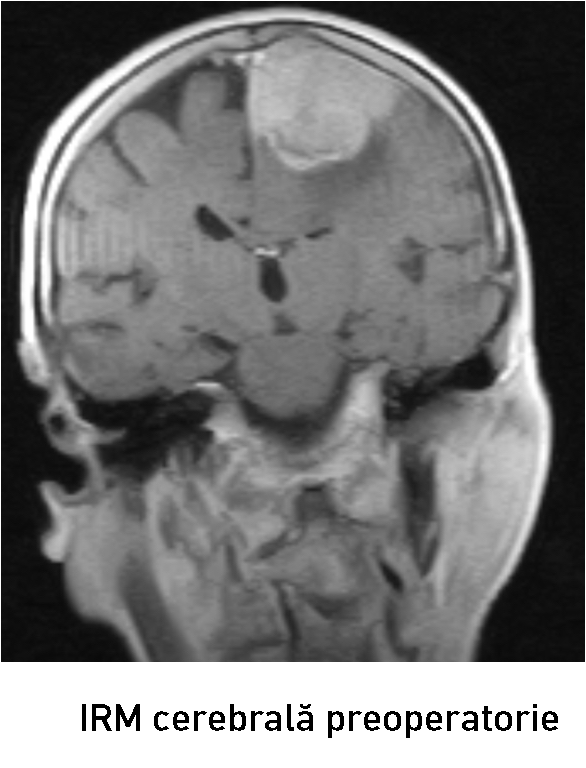

Examenul neuroimagistic prin IRM a stabilit prezența unei formațiuni tumorale intracraniene extraaxiale pe stânga (6

Examenul neuroimagistic prin IRM a stabilit prezența unei formațiuni tumorale intracraniene extraaxiale pe stânga (6

6 x 37 x 45 mm)la nivelul parasagital (1/3 medie a SSS) ce comprima regiunea precentrală și postcentrală stângă (fig. 1-2). Formațiunea de volum era atașată de sinusul sagital superior, de coasa creierului și capta intens substanța de contrast – suspect pentru un meningiom parasagital voluminos. Luând în considerație volumul leziunii tumorale, se impunea realizarea tratamentului neurochirurgical.